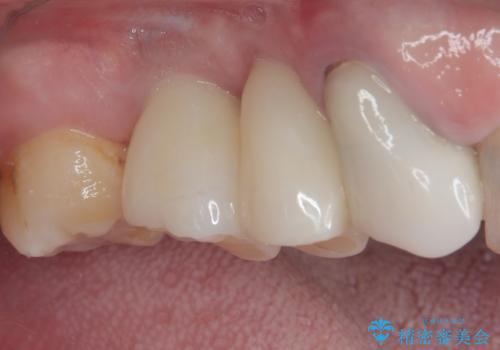

本来であれば、下顎の歯列を整えることで、上下がタイトに咬み合わせるように仕上げるべきでしたが、予算の都合で上顎のインプラント補綴治療のみを行うこととなりました。